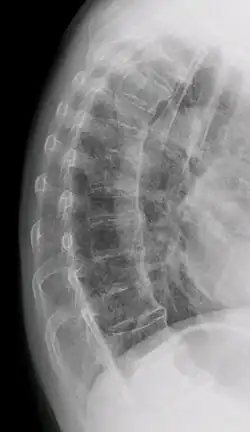

Confluent ossification of multiple contiguous vertebral bodies in diffuse idiopathic skeletal hyperostosis (DISH) -

"Melted candle wax" appearance of calcification and ossification in diffuse idiopathic skeletal hyperostosis (DISH). Note the preponderance on the patient's left side (right side of image). -